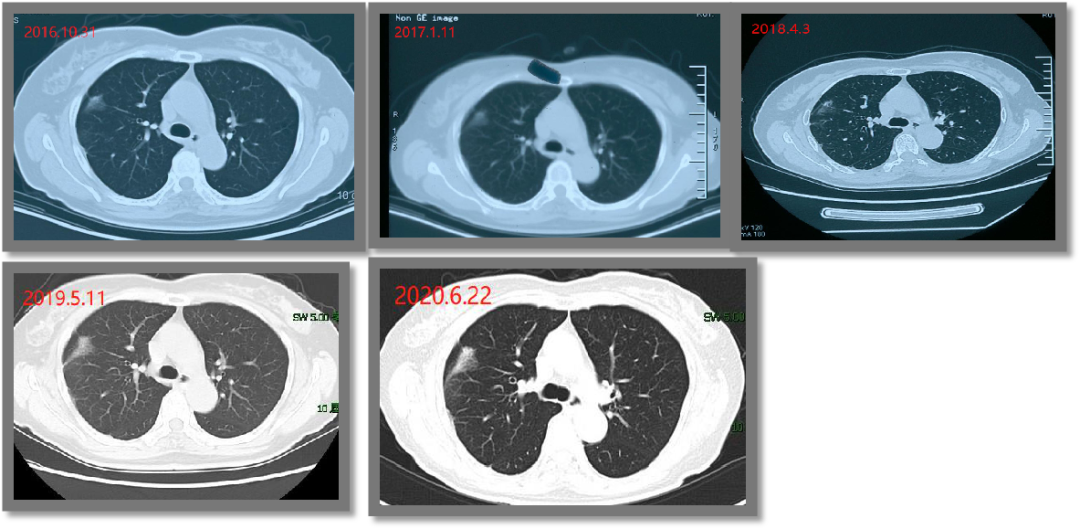

而直到今年8月,结节才终于做微波消融打掉,并取到了满意的病理:原位腺癌。

14年的随访,对张女士的身体和精神来说,无疑都是一场持久战。和伴随自己十几年的结节终于告别后,她无比庆幸自己等到了微波消融微创治疗手段,心里的大石头落了地,再也不用提心吊胆过日子了!

图2 张女士术前、消融中、消融后三个月复查结果